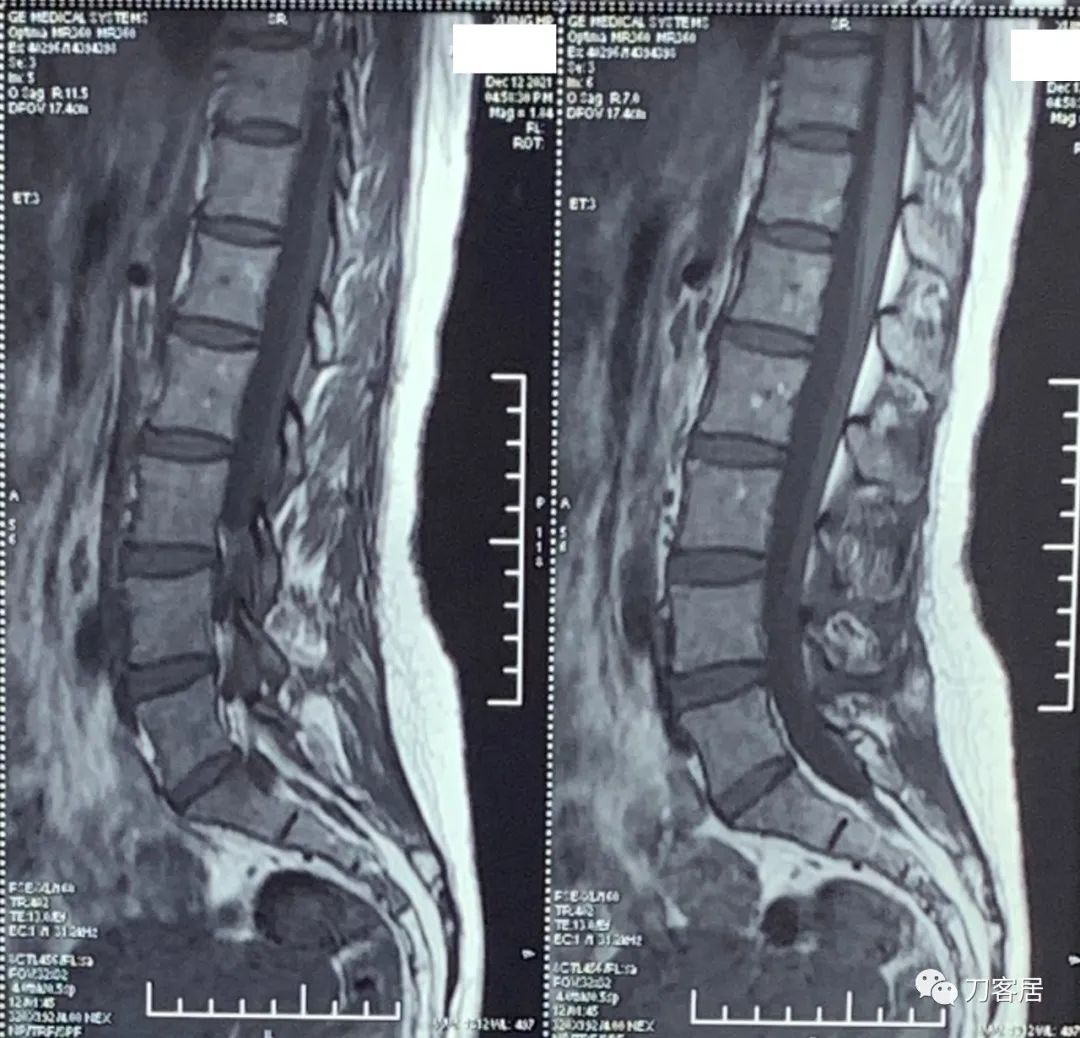

自带腰椎MRI检查未见异常。腰椎X线片提示左侧腰5横突肥大。自带外院骨密度检查结果正常。

20211212西京医院腰椎MRI.